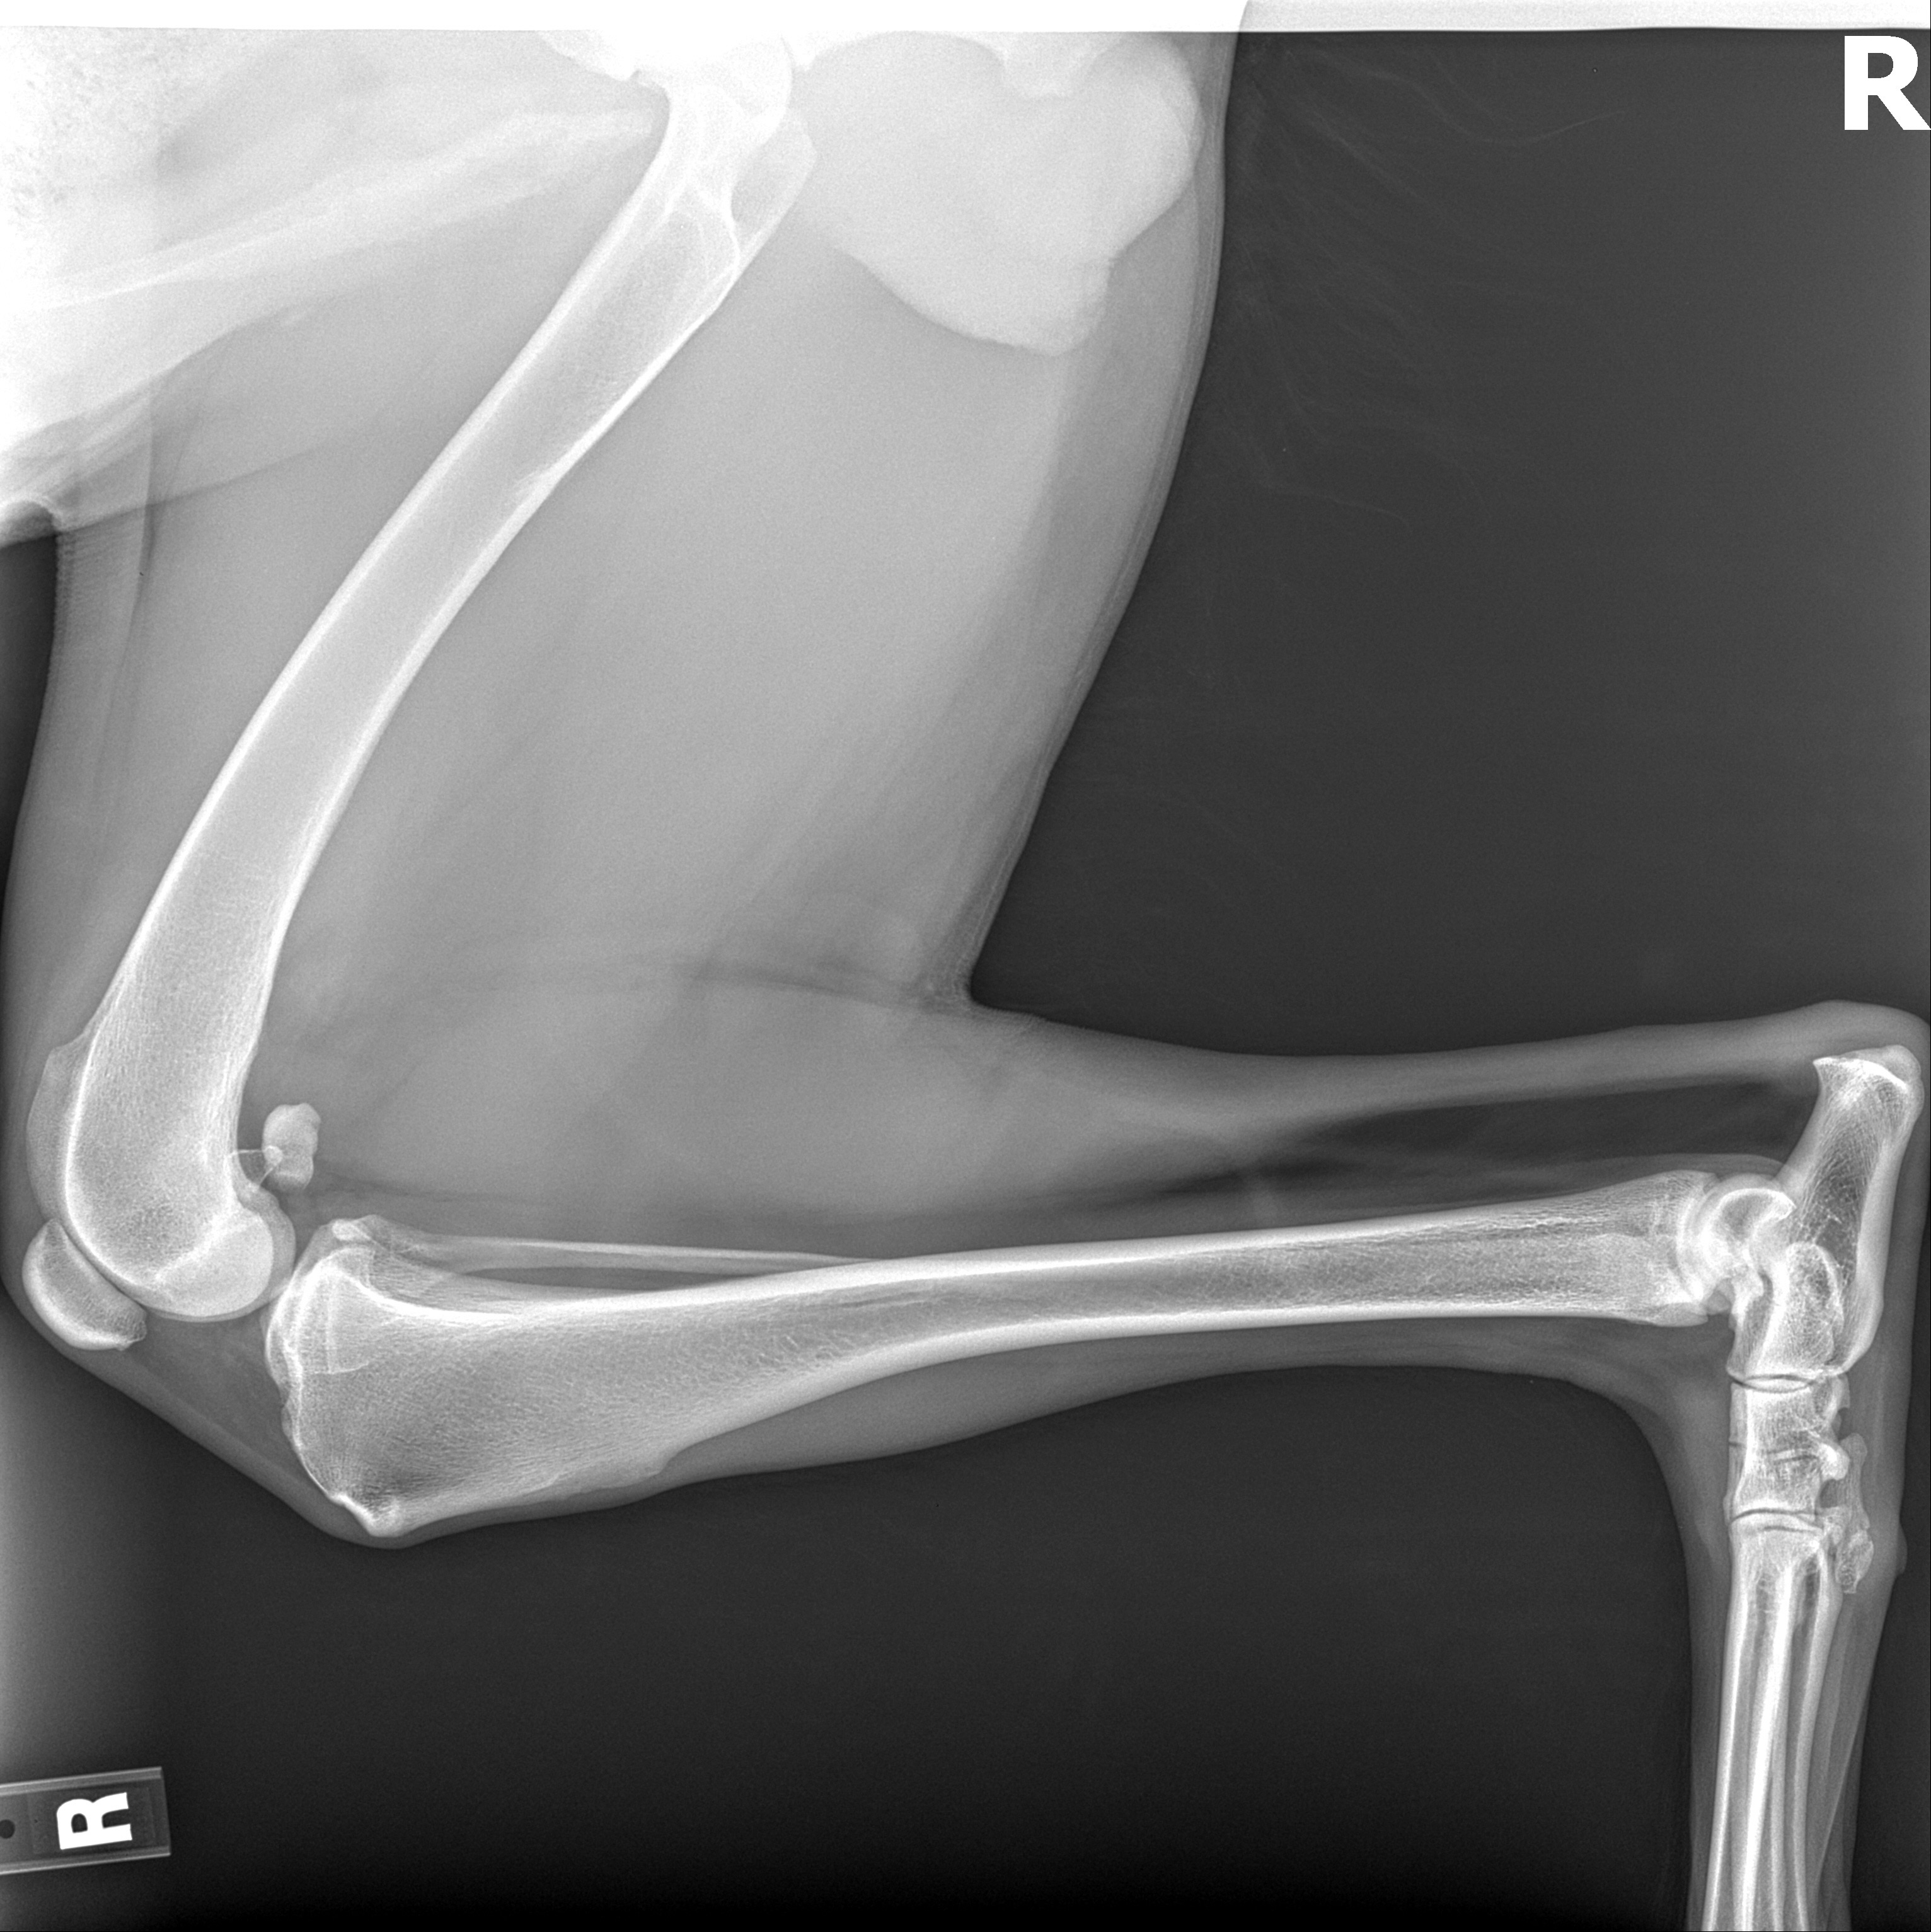

Sadly, Gaylen has been diagnosed with bone cancer. His pain is now not manageable. It seems to have spread from his leg to his hip. For now, pain medication and D8/CBD seem to be keeping him content until we can schedule a time with the vet to help him move on.